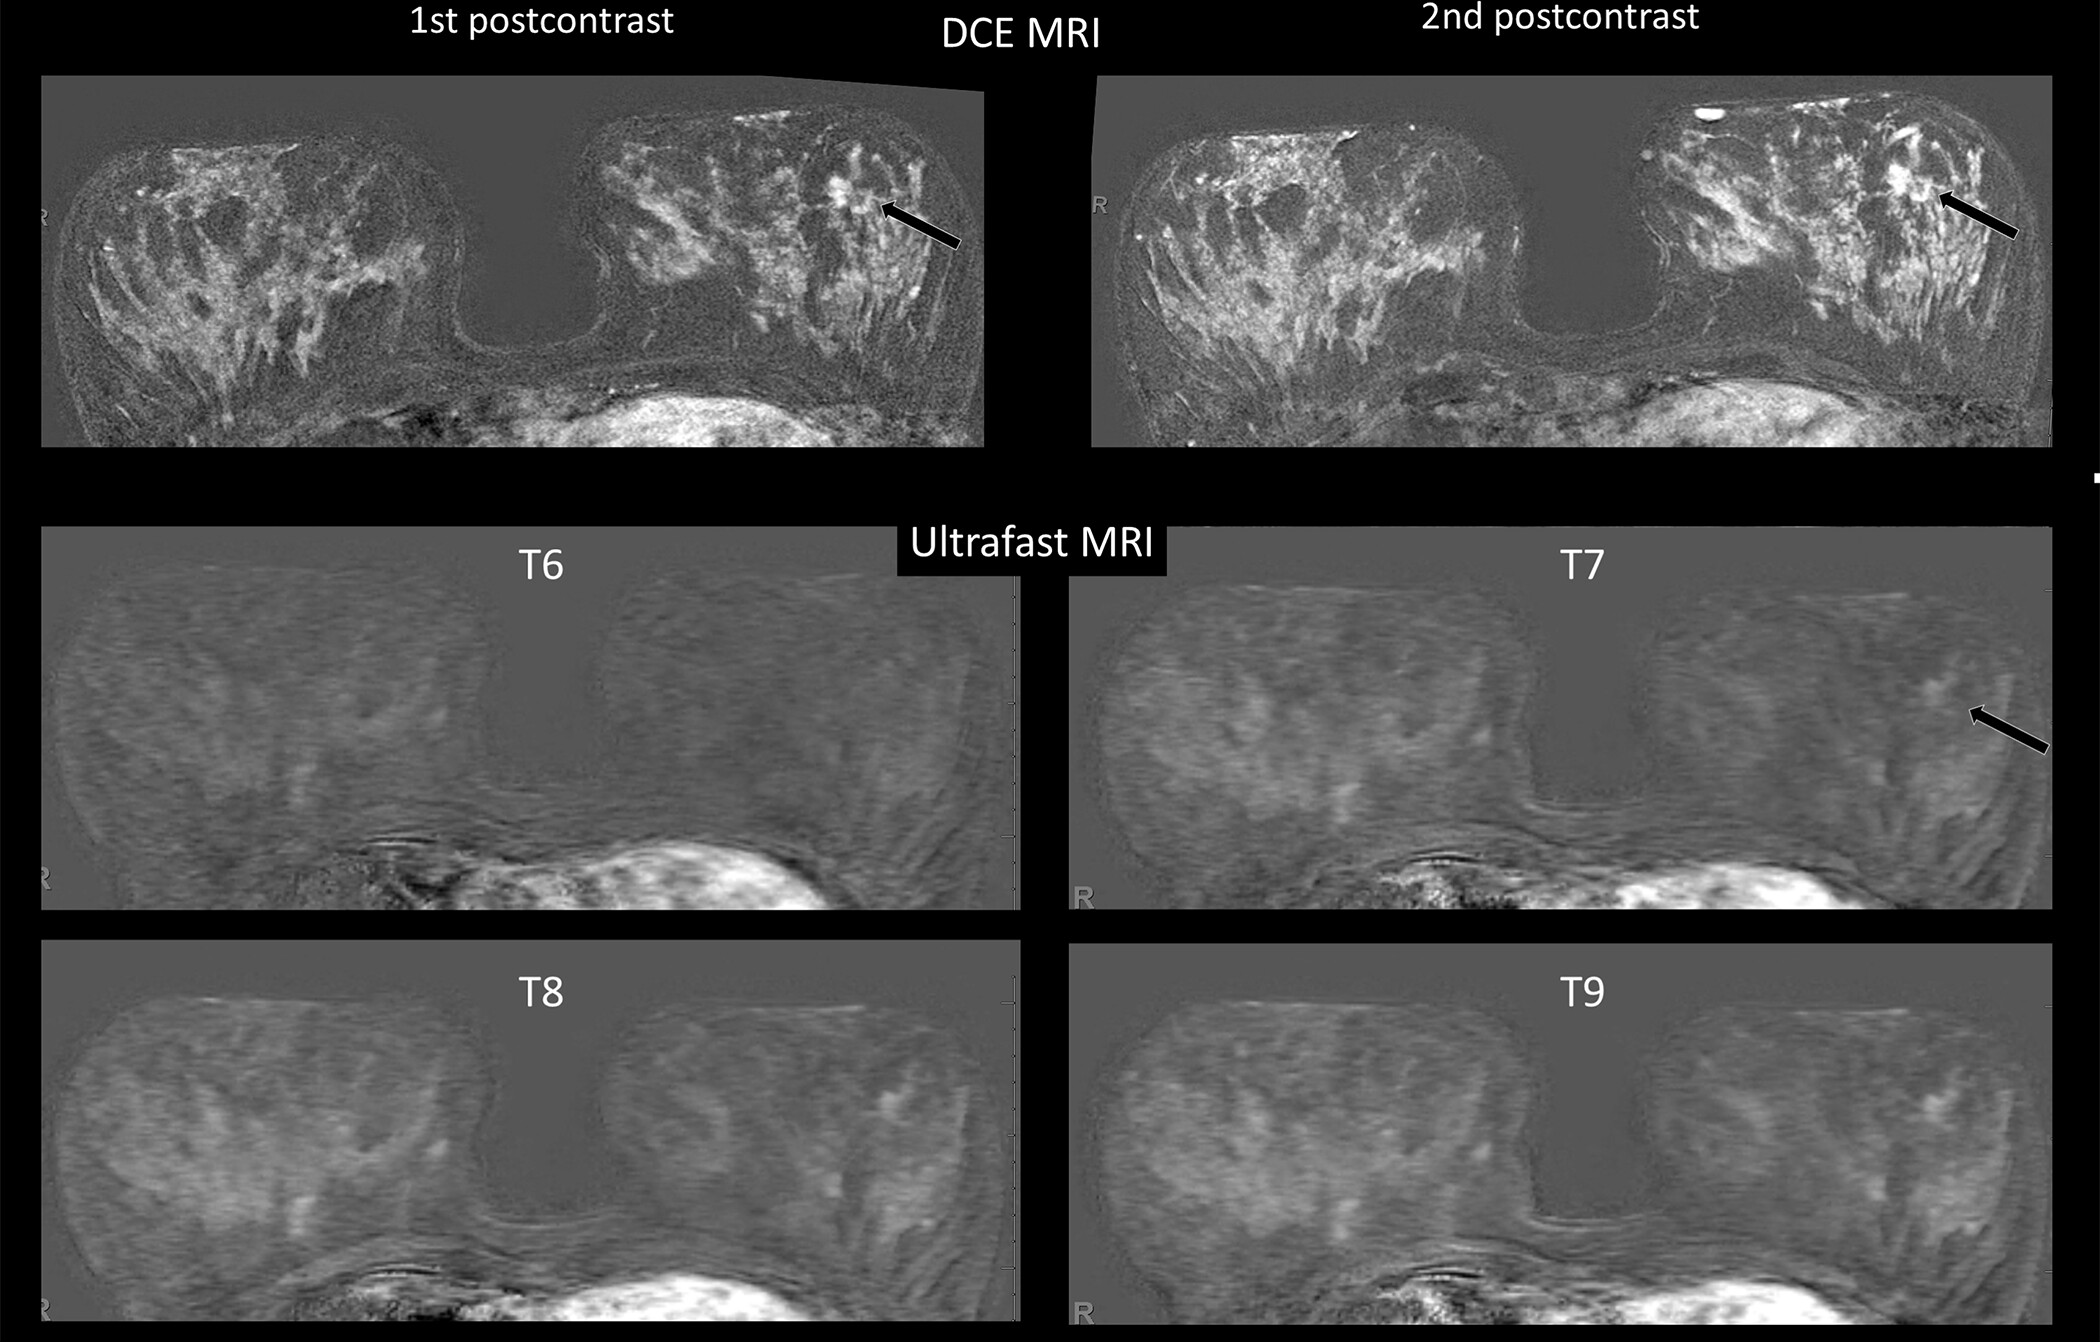

Diagnostic Imaging: Breast, 2nd Ed. ― Published by Amirsys。Breast Imaging 2 Fall 2025 | Canadian Association of Medical。Quantra® 2.2 | Breast Density Assessment Software | Hologic。マンモグラフィーや超音波などの診断技術を網羅した、拡大改訂版の医学書。Computer-aided detection enhances breast MRI | AuntMinnie。- 書籍名: Diagnostic Breast Imaging- 著者: Sylvia H. Hewayng-Köbrunner, D. David Dershaw, Ingrid Scherer- 版: 第2版, 拡大改訂版- 出版社: Thieme- 内容: マンモグラフィー、超音波、磁気共鳴画像、介入手技に関する情報ご覧いただきありがとうございます。。